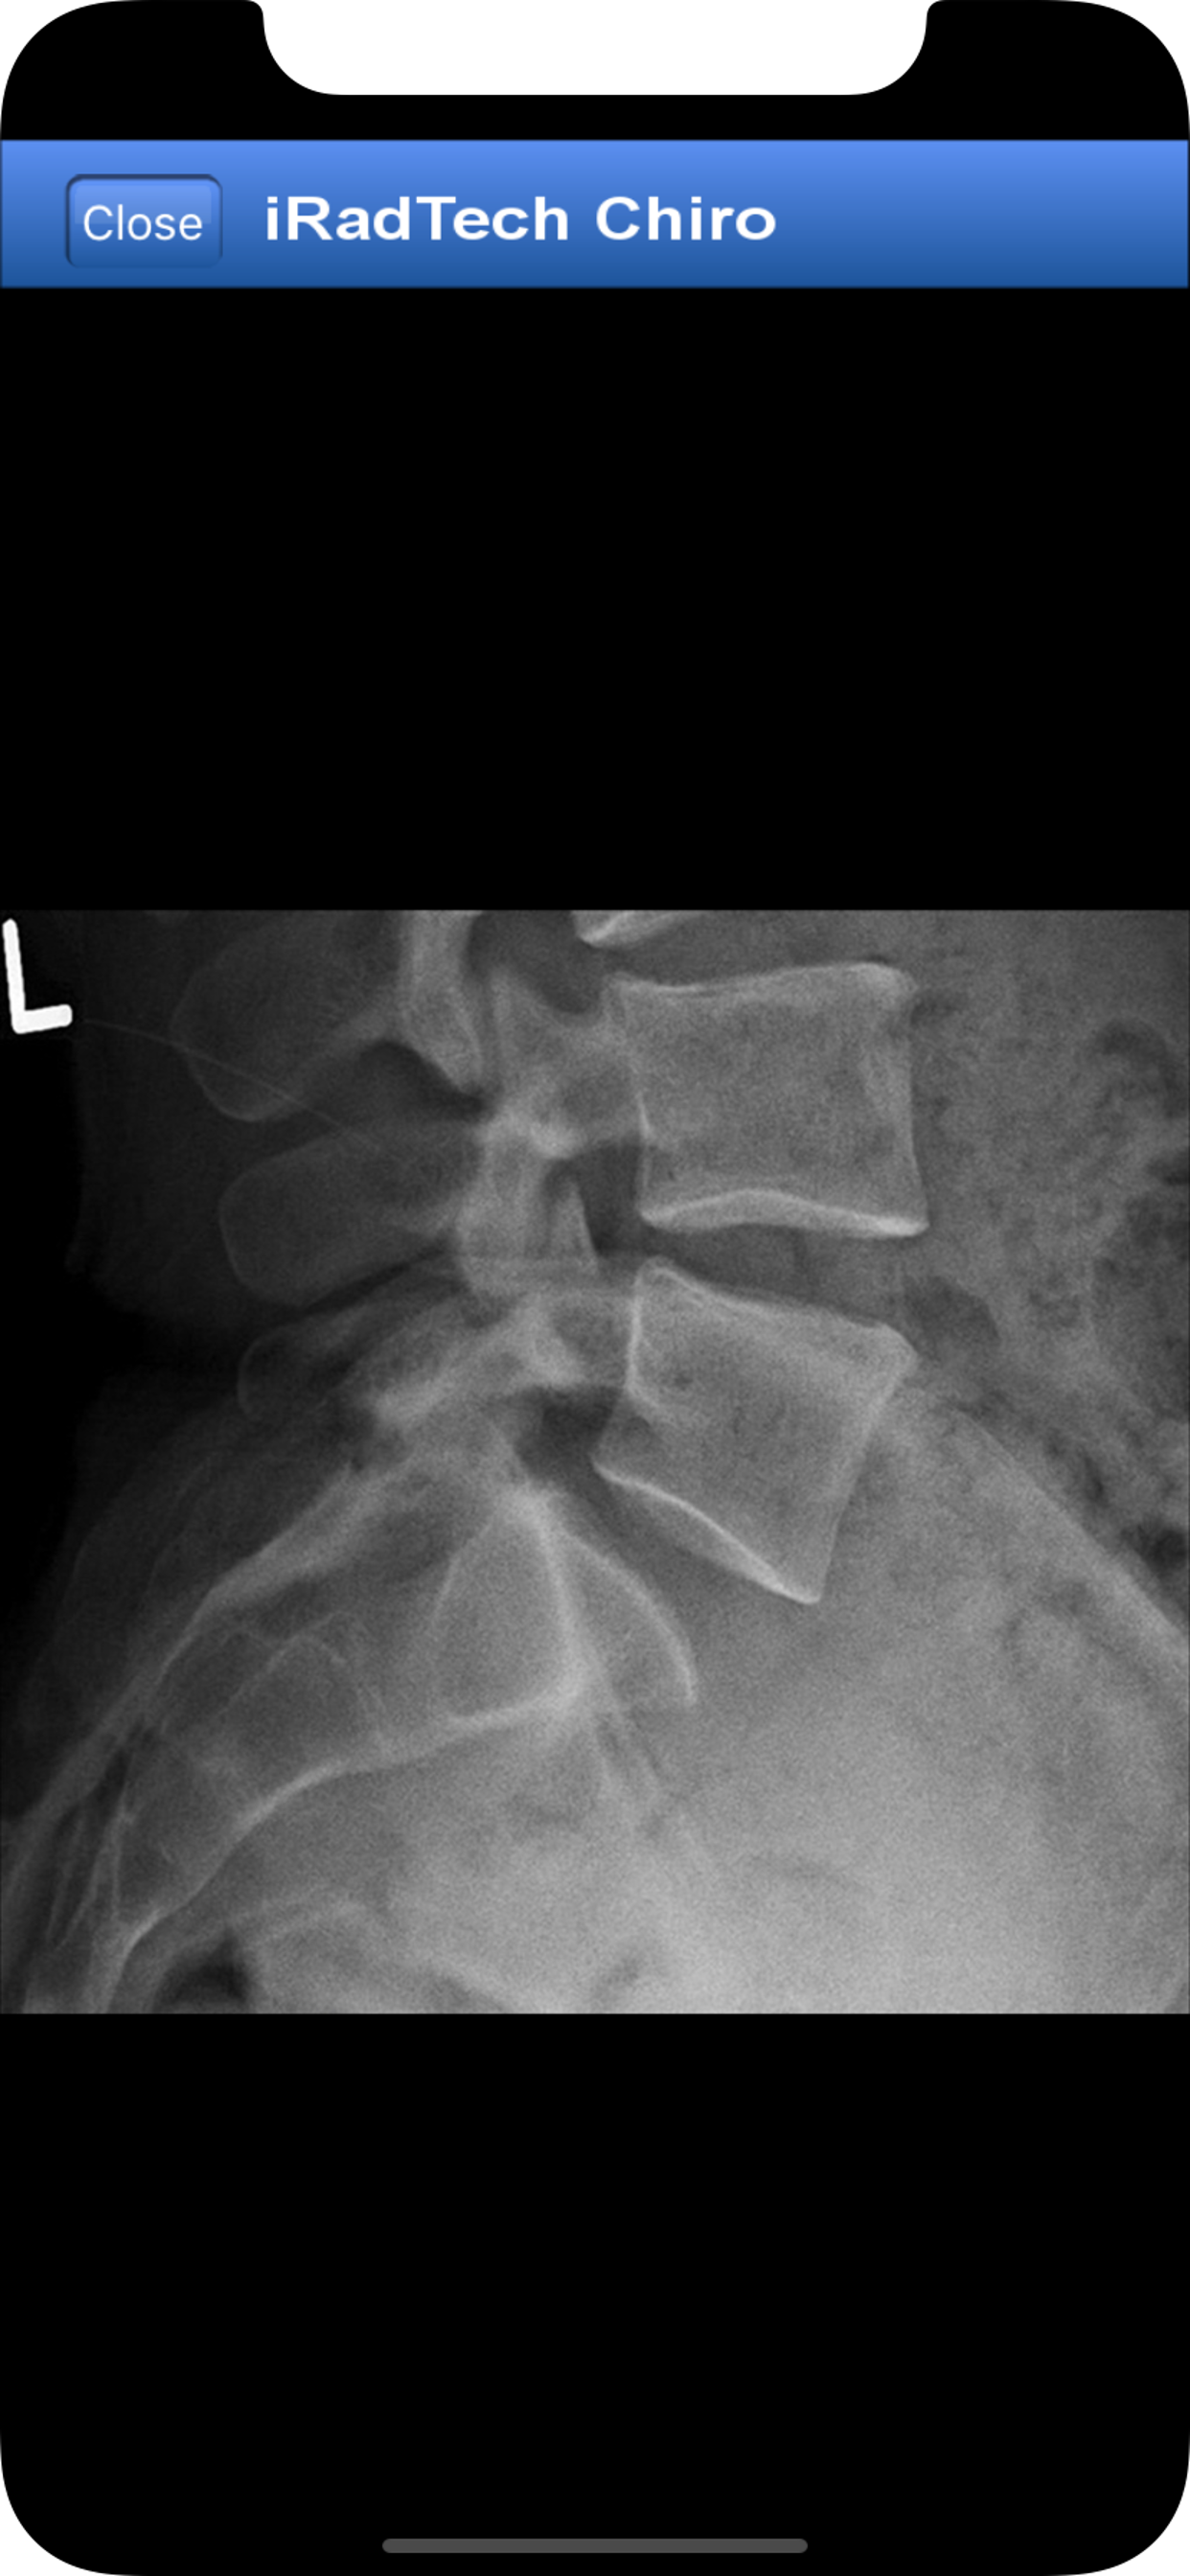

iRadTech Chiropractic Radiography for iPhone and iPad iRadTech Chiro is a positioning guide for the Chiropractic Radiographer. The app describes the positions relevant to chiropractic practices, the steps involved to perform each, evaluation criteria for the image, plus other important procedural details. Practicing and student radiographers will find iRadTech Chiro a convenient and accurate reference. Students will also find it a great study tool. iRadTech Chiro includes: • More than 115 radiographic positions written with Chiropractors in mind • Expandable positioning and radiographic images • Detailed instructions on how to position the patient and what to look for in the resulting image Position instruction subheadings: • Technical Factors • Image Receptor • Patient Position • Body Part Placement • Respiration • Central Ray • Image Quality Points • Structures Demonstrated chiropractic, chiropractor, radiologic technology, rad tech, medical, imaging, xray, x-ray, radiology, radiography